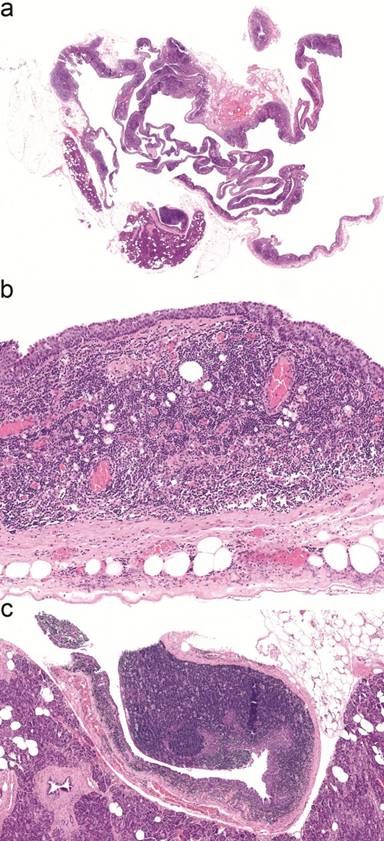

Histopathological examination (Figure 3) of the resected specimen revealed a completely excised multiloculated cyst measuring 60×30×10 mm lined with squamous epithelium with a transitional appearance and containing abundant lymphocytes in the wall, all consistent with a lymphoepithelial cyst. There was no evidence of dysplasia or malignancy.